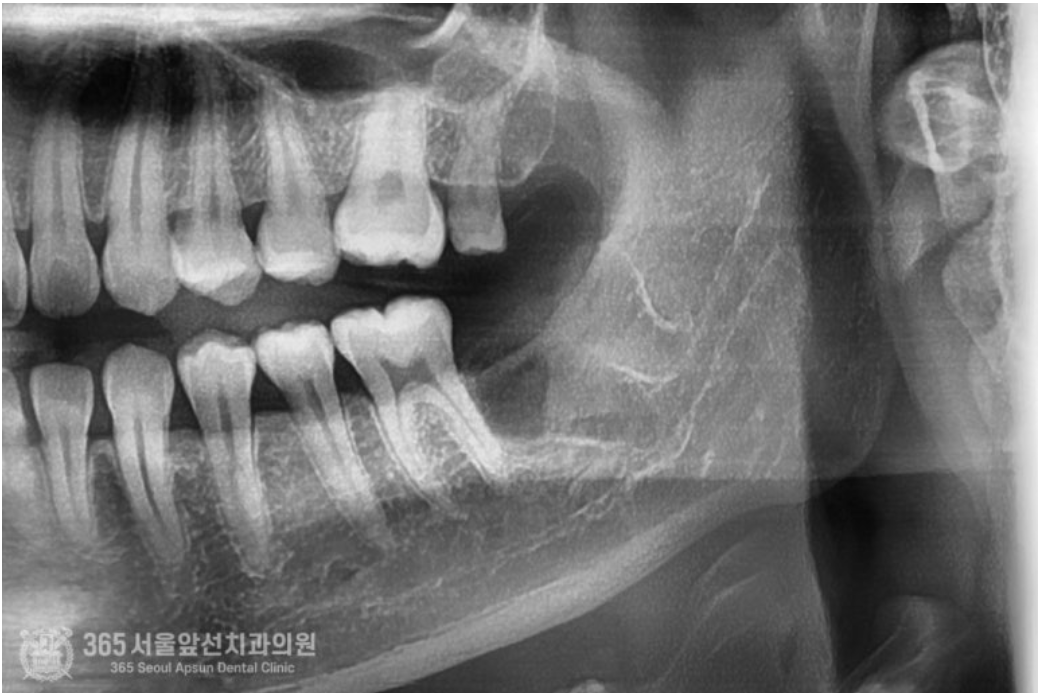

안녕하세요. 주안동치과 365서울앞선치과의원입니다. 오늘은 심각하게 매복된 사랑니 발치에 대한 치료증례를 살펴보겠습니다. 동네 치과에 가셨는데 신경과 거리도 너무 가깝고 매복도가 심해서 대학병원에 내원하셔서 발치하도록 권유받았다는 환자분께서 오셨습니다. 일단 엑스레이와 CT를 찍고 진단을 해봅니다 ㅎㅎ 환자분께서 너무 걱정하시더라구요. 걱정마세요. 어떤 사랑니도 자신있습니다 !! 촬영일시 : 2024.06.03. 처음 내원 당시 사진입니다. 어금니와 사랑니가 꼬여있고 매복되어있네요 ㅠㅠ 안전하고 신속한 발치를 위해서 CT까지 찍습니다. 촬영일시 : 2024.06.03. CT 입니다. 사랑니가 혀쪽으로 매복되어있고 신경관에 뿌리가 박혀있군요. 자 이제 발치를 시작해봅니다 ㅎㅎ 안전하고 신속하게 빼드렸습니다 ㅎㅎ 촬영일시 : 2024.06.03 발치된 치아들이구요. 매복발치이기에 치아를 분할하여 발치하였습니다. 촬영일시 : 2024.06.03 발치 후 엑스레이 사진입니다. 발치된 자리가 선명하게 보이네요 ㅎㅎ 안전하고 신속한 발치를 추구하는 치과의사 강동우였습니다. 더 좋은 치료증례로 찾아뵙겠습니다! [ 치료기간 : 치료기간: 2024년 6월3일 ] ※ 365서울앞선치과의원의 모든 포스팅은 각 진료과 의료진이 직접 작성합니다. 365서울앞선치과의원 블로그의 임상 케이스 게시물은 환자분께 의학적으로 정확하고 상세한 정보를 드리기 위해 각 진료과 의료진이 직접 작성하며, 모든 증례 사진은 본원 의료진이 직접 시술한 증례를 촬영한 것으로, 의료법 제23조, 제56조에 의거하며 환자분의 동의를 얻어 포스팅에 사용하였습니다. 또한 해당 케이스는 본 환자분의 치료 결과이며, 환자 상태에 따라 치료의 결과는 달라질 수 있습니다. |